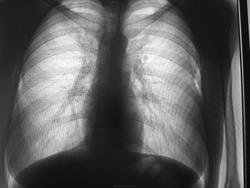

Проф флг, 1998 гр, есть ли расширение правого предсердия или за счет ассиметричной укладки?. Смущает правый корень: как будто высоко расположен, высоко отходит верхнедолевой бронх. Архива нет.

Проф флг. Участки "просветления" в боковых отделах средних легочных полей - за счет контраста с тенями молочных желез?

Проф флг, 2 тени над 1 ребром слева - тени сосудов? Архива нет.

Проф флг, тени с неровным четким контуром в 5 м\р с обеих сторон, в архиве - тень в 5 м\р справа меньших размеров (2 последних снимка). Или это соски такие?

№1 - не раскрывается, но из того, что удалось рассотреть - асимметричная установка, думаю, отсюда и проблема. На остальных флюорограммах патологических изменений не нашла. Молочные железы, сосуды, соски - Вы правы.

Да, у №1 - не корректная установка (посмотрите на ключицы.)

Меня учили, что расположение корней определяется относительно друг друга. Верхний уровень отхождения правого ВДБ должен соответствовать верхнему краю лев. легочной артерии. Отношение корней к ребрам - это дело второстепенное.

Не слишком ли коллеги упрощают жизнь автору ветки? Я бы в последнем случае порекомендовал дообследование: оба бока.

"Участки "просветления" в боковых отделах средних легочных полей - за счет контраста с тенями молочных желез?"

- Тени кожных складок у основания молочных желёз.